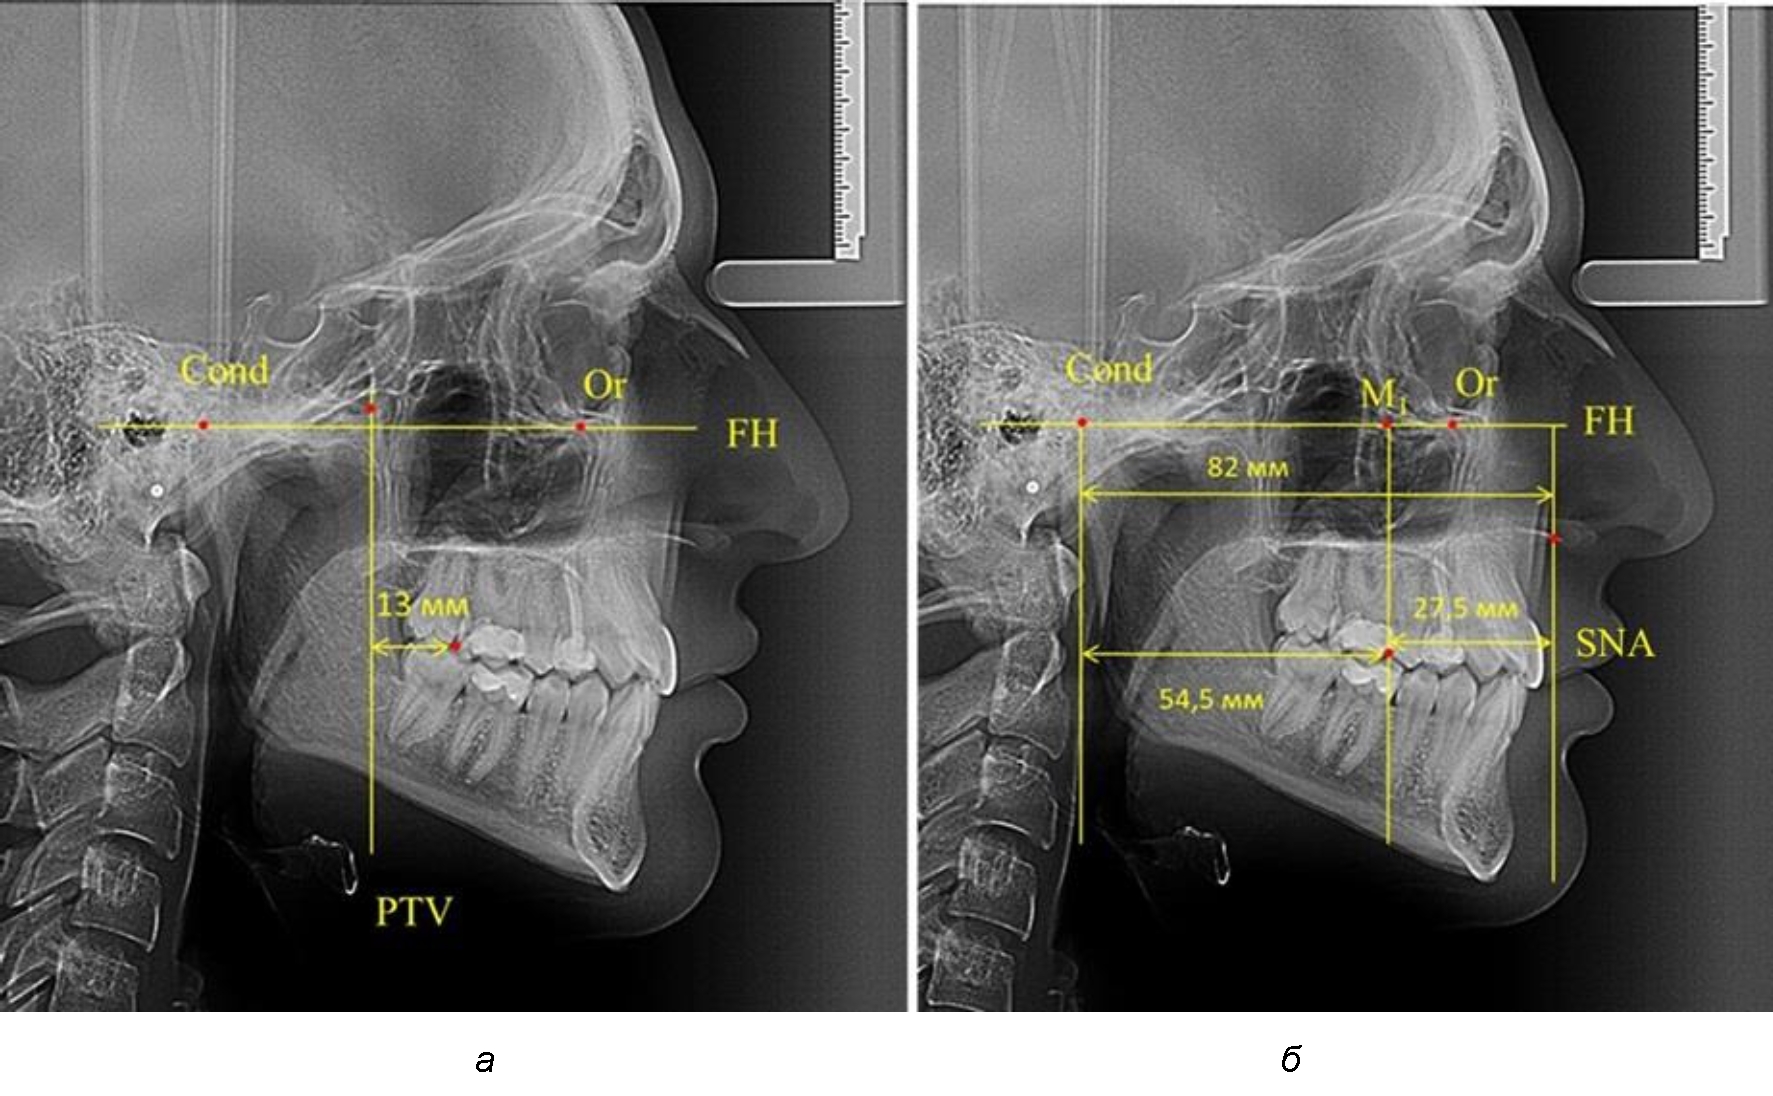

Рис. 1. Метод определения положения первых верхних моляров по Ralph E. McDonald (а) и по предложенному методу (б)

Так, при расстоянии от крыловидной вертикальной плоскости PTV до дистальной поверхности верхнего первого постоянного моляра в 13 мм сагиттальный размер гнатического отдела был 82 мм. При этом отношение кондилярно-спинального расстояния к кондилярно-молярному размеру (54,5) было близким к коэффициенту 1,5, что представлено на рис. 2.